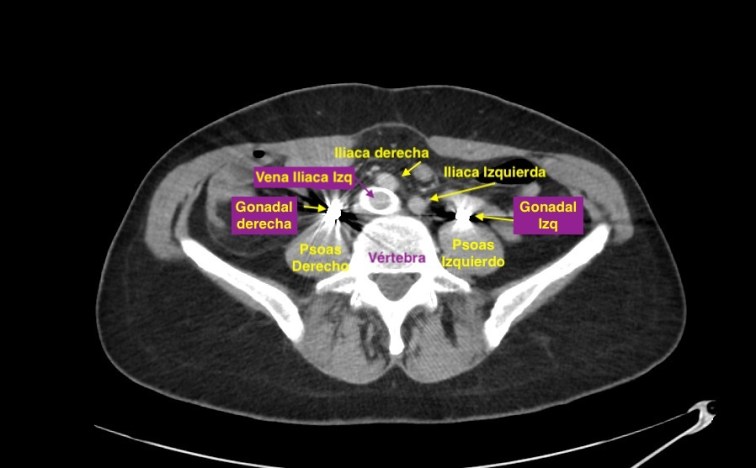

Es una afección en la cual la vena ilíaca izquierda en la pelvis se comprime por la arteria ilíaca derecha que pasa justo por encima de ella. Aumenta considerablemente el riesgo de trombosis venosa profunda (TVP) en la pierna izquierda.

En el corte axial de las imágenes 3 y 4 puedes ver la anatomía radiológica implicada. La relación es perfecta, y completamente explicativa de la situación resulta mediante el tratamiento quirúrgico. En ella la Arteria iliaca derecha para justo por encima de la Vena iliaca Izquierda con la capacidad de poder comprimirla.